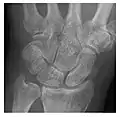

High-energy trauma fractures

Occult osseous injuries may result from a direct blow to the bone by compressive forces of adjacent bones against one another or by traction forces during an avulsion injury. Lesions in the tibial plateau, hip, ankle, and wrist are often missed. In a tibial plateau fracture, any disruption of the posterior and anterior cortical rims of the plateau should be sought. Impaction of subchondral bone will appear as an increased sclerosis of the subchondral bone (Figure 1). In the hip, posterior acetabular fractures also present subtle radiographic findings. The acetabular lines should then be carefully examined keeping in mind that the posterior rim, which is harder to see on X-rays, is more frequently fractured than the anterior rim (Figure 2). In the wrist, detection of carpal bone fractures is often challenging, with up to 18% of scaphoid fractures radiographically occult. Carpal fractures, especially the scaphoid, are associated with the risk of avascular necrosis. In apparently normal wrist radiographs from symptomatic patients, if there is history of a fall on an outstretched hand with pain in the anatomic snuffbox, suggesting scaphoid injury, the initial examination with posteroanterior, lateral, and pronation oblique views must be complemented by other specific views such as supination oblique and the "scaphoid" view A careful examination of cortices for evidence of discontinuity or offset and cancellous bone for lucency is necessary (Figure 3).[1]

Figure 3: A 26-year-old man presenting with wrist pain after being assaulted. (a) Initial anteroposterior radiograph shows a subtle linear lucency within the scaphoid extending to the scaphocapitate articular surface that was overlooked (arrow). (b) Initial "scaphoid" view was negative. (c) Followup anteroposterior radiographs, 12 days later, shows obvious scaphoid fracture (arrows).[1]